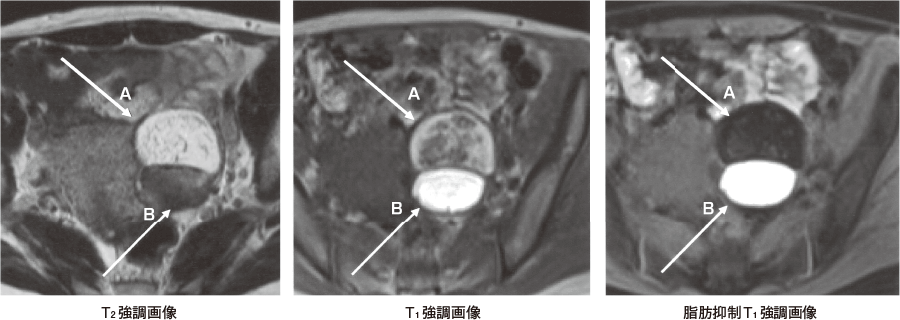

医師がそれを発見すると、画像検査を指示する可能性があります。好ましい検査は経膣超音波の使用です。通常、超音波検査で奇形腫がどのように現れるかに基づいて奇形腫を特定できます。